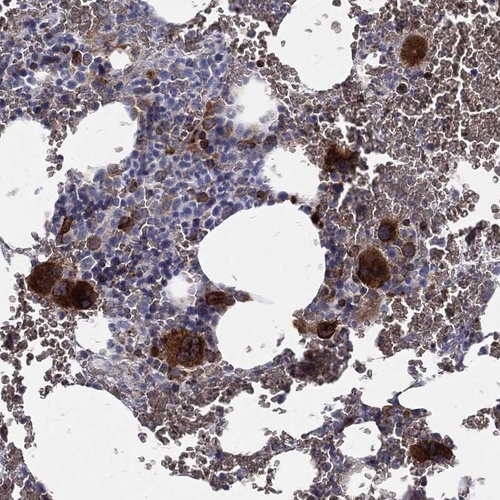

Immunohistochemical staining of human bone marrow shows strong cytoplasmic positivity in hematopoietic cells.